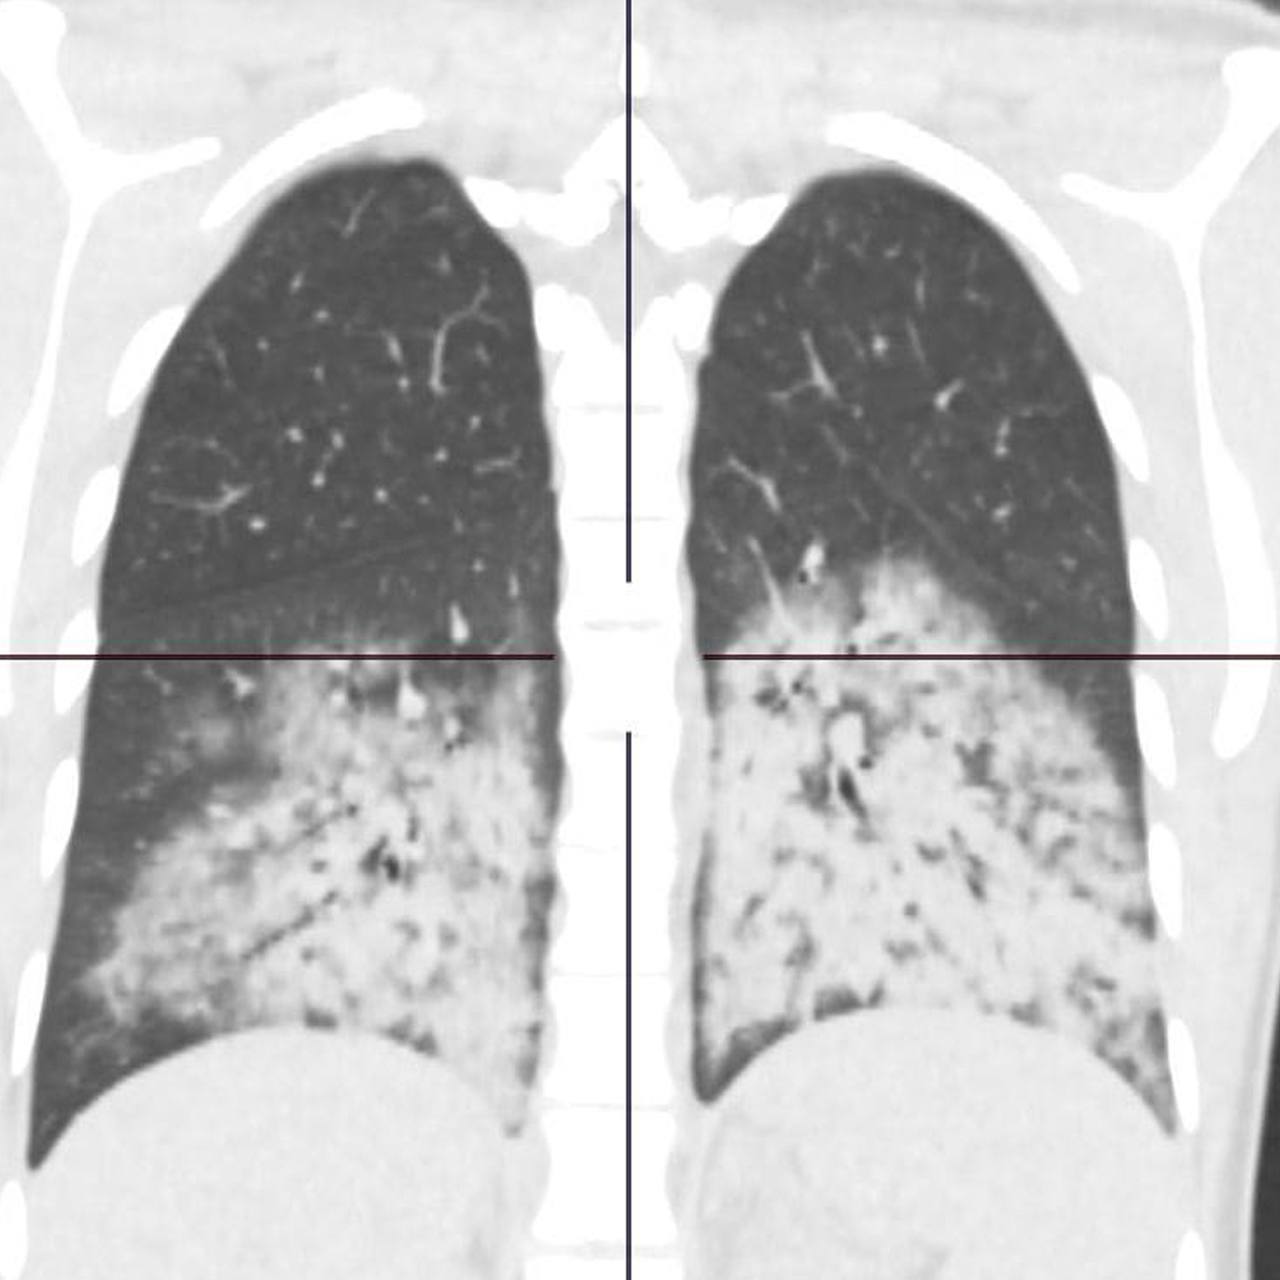

Как лечить evali

Как лечить evali 106 фото